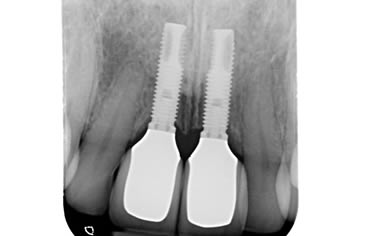

More front teeth replaced by dental implants

Case Three (4 images)